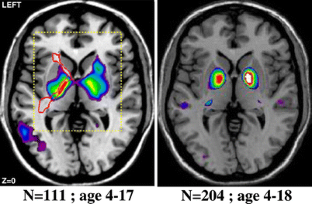

Brain imaging research with MRI spans a wide area, covering both structure and function, and ranging from basic research through clinical research to drug design and clinical trials. In recent years there has been a trend towards the collection of very large MRI databases which can allow for the detection of very small group-dependent effects. However, the logistical challenges of analysing such large datasets presents new challenges. This paper describes the “pipeline” framework developed at the Montreal Neurological Institute for the fully automated morphometric analysis of large brain imaging databases. The potential use of these techniques is illustrated by examples of their applications in multiple sclerosis, Alzheimer’s disease, and pediatric development.

Fig. 1